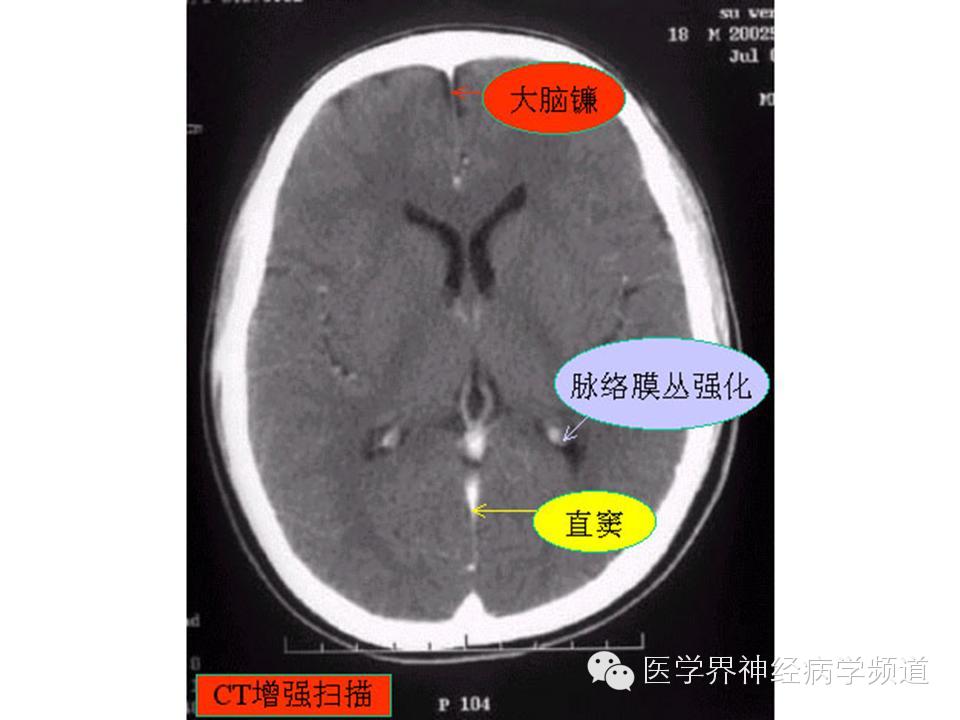

神经影像CT读片step by step